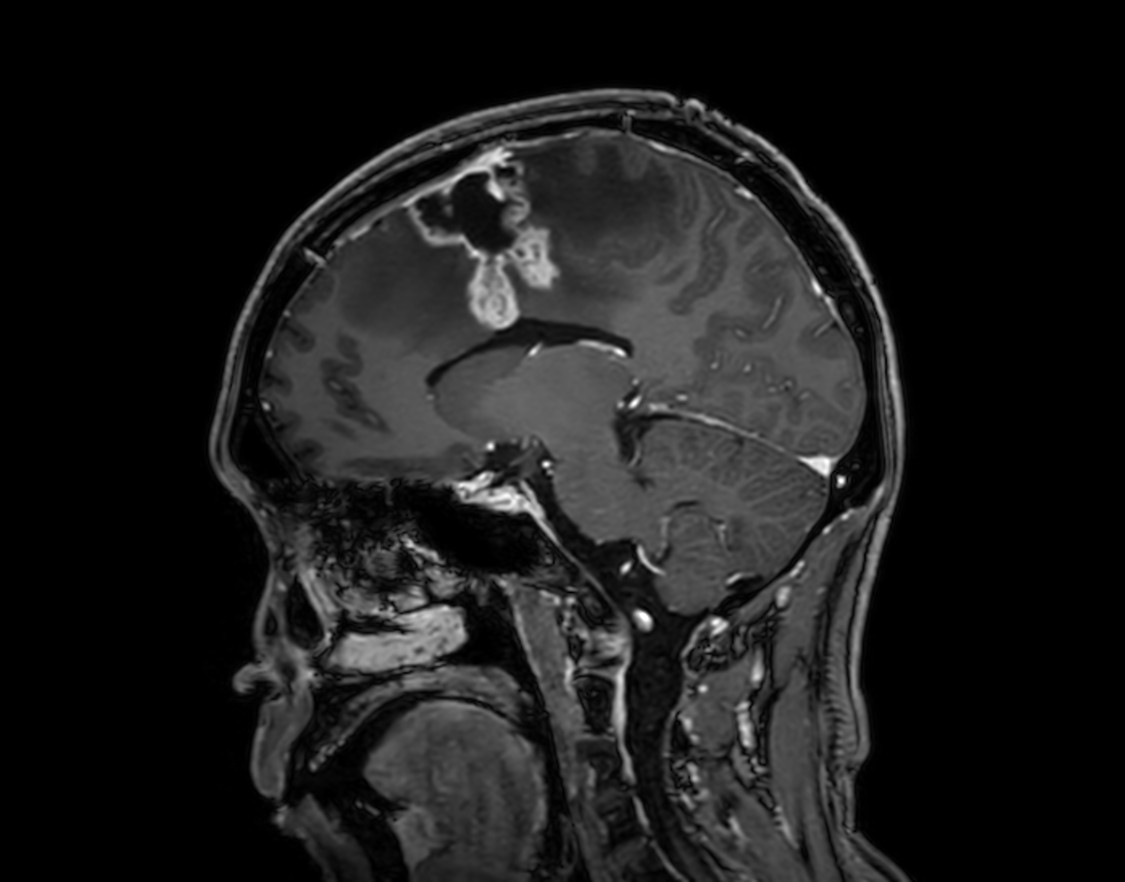

SmartSpeed Precise imaging for brain with glioblastoma

Kyushu University Hospital Japan